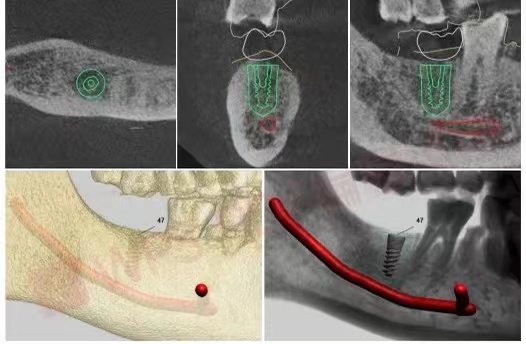

在进行了全面的术前检查和评估之后,医生会将完整数据上传到UNIC全息数字化会诊系统中,以数字化全息影像为基础的方案设计更形象、更易懂。

在UNIC数字化种植方案设计中心,杨勇主任耐心的为白叔叔讲解。根据全景牙片可以看到,白叔叔的右侧下颌第二磨牙缺失,影响右侧咀嚼功能。

CBCT三维立体全景影像片及术前模拟

这打消了他的担心和疑虑,同时通过直观可视的导板设计界面白叔叔看到了模拟的手术过程及预测的术后效果,让叔叔对手术更有信心。

为白叔叔设计的种植方案